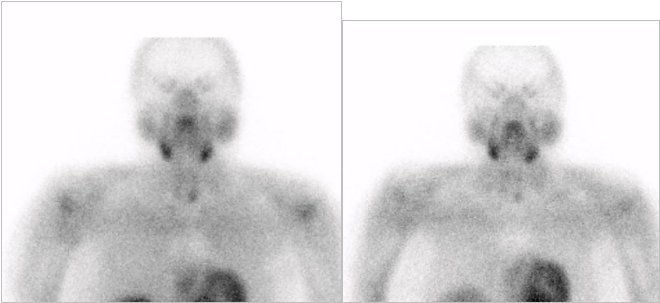

/ Obr. 1.: Planární scintigrafie v AP projekci pomocí 99mTc-MIBI (1.fáze vlevo, 2.fáze vpravo), kde je zachycena oblast zvýšeně akumulující radiofarmakon

(Tc-MIBI)

se zpomaleným vymýváním vlevo s projekcí do úrovně dolního pólu levého laloku štítnice.

Při planárním snímkování nalézáme zřetelnou ložiskovou oblast zvýšeně akumulující Tc-MIBI při dolním pólu levého laloku štítné žlázy. Dochází rovněž ke zpomalenému vymývání radiofarmaka z této oblasti. Pomocí SPECT/ldCT upřesněna lokalizace do dolního PT vlevo.